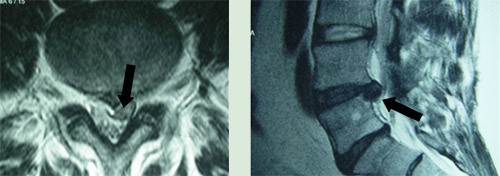

As hérnias lombares (Figura II) são as mais frequentes e as dorsais as mais raras. Na origem das hérnias discais estão fragilidades individuais, movimentos bruscos de extensão e/ou torção do tronco, execução de esforços ou o levantar de pesos com a coluna fletida, além da existência de outros fatores, como os erros posturais, sedentarismo, etc. Também a obesidade, pelo excesso de peso, e o tabagismo, pelas alterações que acarreta na micro-vascularização arterial, são fatores condicionantes do desenvolvimento das hérnias discais.

Figura II: As setas indicam a hérnia lombar entre a L4 e a L5